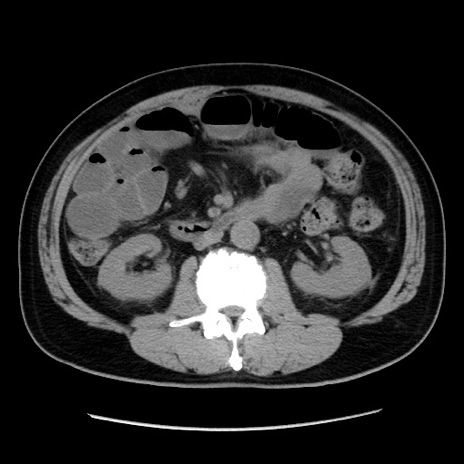

冠状断像

【現病歴】 約1ヶ月前より間欠的に腹痛と嘔吐あり、当院消化器内科を受診したところCTで多発する肝臓のLDAを指摘され、精査中であった。以降は消化器症状は安定していたが、2日前より嘔気と腹痛があり、同日より排便・排ガスが消失した。改善認めず、 本日、救急外来を受診した。